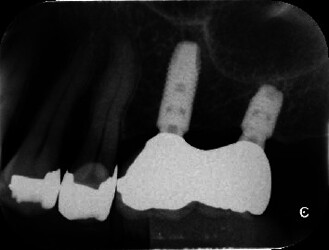

A 3-year study evaluating short (6 mm) and Longer Implants Placed Side by Side in Posterior Partially Edentulous Area concluded that: Clinical outcomes of 6 mm short implants and conventional implants placed under similar conditions of bone quality and occlusal loading were analyzed in terms of MBL changes, survival rates, and the other biological or prosthetic complications. Within the limits of this study, it can be concluded that short implants in a posterior edentulous region showed excellent results compared with conventional implants.

Intraoral radiographs showing after 3 years of loading. One short implant and one standard-length implant were placed next to each other.Source: - Clinical Evaluation of Short (6 mm) and Longer Implants Placed Side by Side in Posterior Partially Edentulous Area: A 3-Year Observational Study. International journal of dentistry. Volume: 2023, Issue: , 2023 - Masahiro Shimogishi , Sawako Kawakami , Noriko Tachikawa